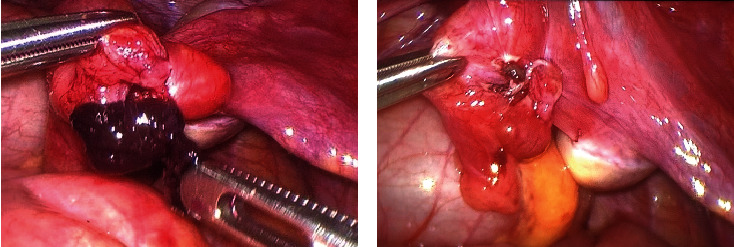

莫加尼水瘤扭转是一种罕见病,可导致年轻女性急性腹痛。我们报告了一例 13 岁女孩因急性腹痛而接受莫氏包虫病扭转治疗的病例。文献中关于 18 岁以下女性患有这种疾病的病例不到 20 例。通过我们按照 PRISMA 声明进行的系统性回顾,我们希望强调诊断的难度,以及在女性急腹症的鉴别诊断中考虑这种病变的重要性,以便及时进行手术治疗,保护这些患者的生育能力。

Torsion of the hydatid of Morgagni is a rare condition which can cause acute abdominal pain in young female. We present a case report of a 13-year-old girl with acute abdominal pain and treated for torsion of the hydatid of Morgagni. Less than 20 cases of female younger than 18 years old with this condition are been described in the literature. Through our systematic review performed following the PRISMA statement, we want to emphasize the difficulty in diagnosis and the importance of considering this pathology in the differential diagnosis of acute abdomen in females with the aim of obtaining a timely surgical treatment to preserve fertility in these patients.